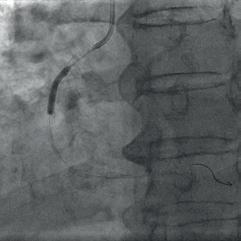

Figure 3c: RCA dilatation with a NC balloon after IVL. Figure 4: Final result after stent implantation.

Due to the possibility of of recoil and the significant risk of vessel reocclusion, we decided to implant two drug-eluting stents – distal-

ly 3.0  26 mm and proximally 3.0  33 mm with minimal overlap. The stents were expanded and a very good angiographic result was achieved with TIMI 3 flow (Fig. 4). The patient was discharged one day later and is doing well. Control coronary angiography for borderline stenosis of the mid LAD with functional assessment of severity is planned.